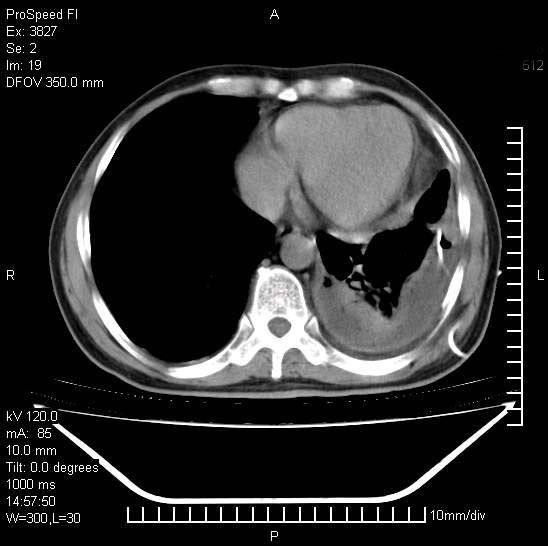

男性,一月前出现右侧肋区疼痛,较剧烈,干咳,无发热,自诉使用抗炎药后缓解,几天前又出现左侧剧烈疼痛,

发热,体温38。9,今天ct,考虑左侧包裹性脓胸,胸腔积液,右上中肺小斑片影,结核/炎症?胸水未见恶性细胞。

左侧肺脓疡,化脓性胸膜炎(脓胸),不支持结核诊断,建议继续抗感染治疗

支持左侧肺脓肿并脓胸,肺内炎症,建议继续抗炎治疗后复查。